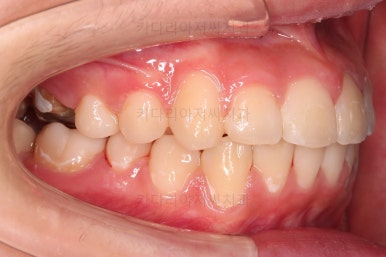

치료 마무리 사진입니다.

연산동치과 전후사진을 비교해 볼게요.

치열이 가지런해지고 교합도 좋아지고 웃는 모습도 매우 좋아졌네요.

비발치 덧니교정이었지만 입이 튀어나오거나 하지 않고 오히려 치아 각도나 입매가 약간 디ㅜ로 들어가면서 입매도 자연스러워졌어요.